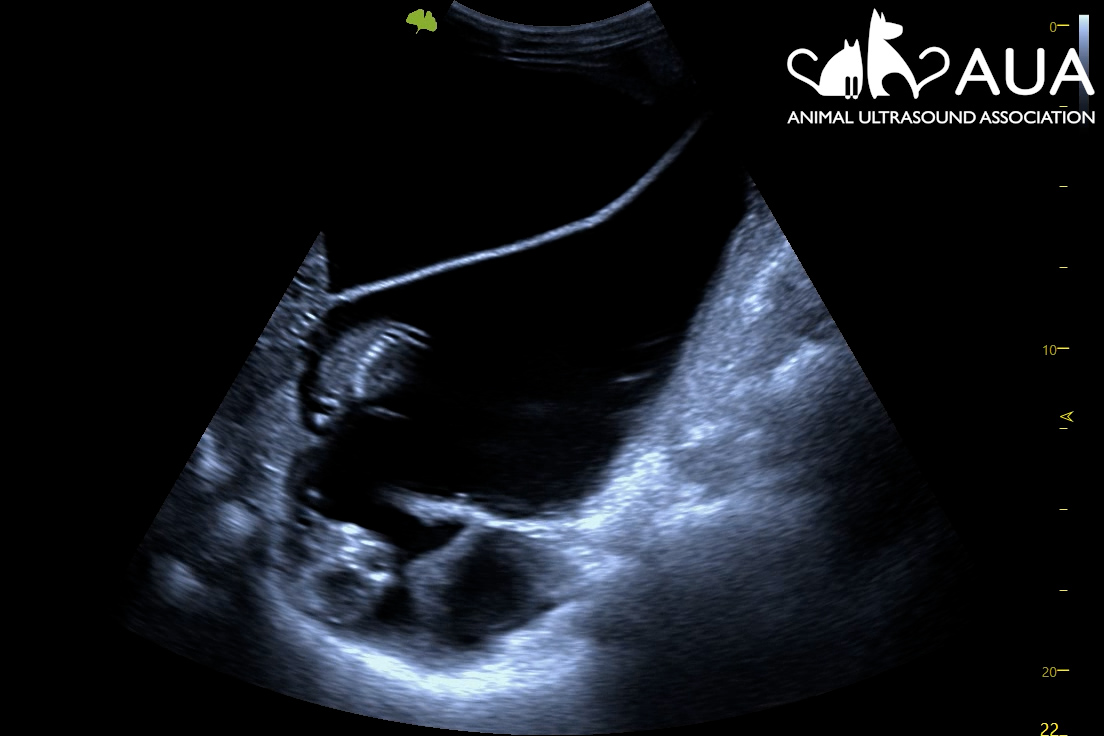

We confirmed 8 pregnancies today in Maidstone, Kent. Most of them were between 50 – 70 days, and it is surprising how tiny the foetus still is even at that stage of gestation. A human foetus at the same gestational age is about 8x larger; a feline fetus, 14x larger! Hence, when scanning you find yourself searching for a pea-sized foetus in a relatively large animal with a large, fluid-filled uterus. This involves moving your transducer along the uterine horns, and fanning back and forth, to try to spot a hiding future cria. At times, this is easier said than done, as alpacas are not always the most still and cooperative when having their abdomens touched.